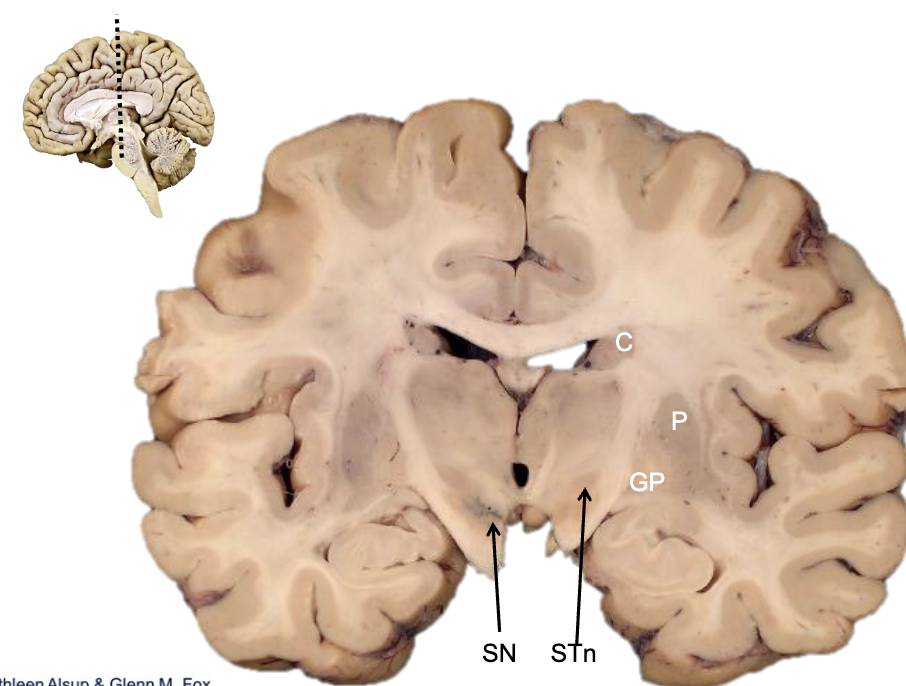

<p><strong>what is c?</strong></p>

what is c?

caudate

<p><strong>what is p?</strong></p>

what is p?

putamen

<p><strong>what is gp?</strong></p>

what is gp?

globus pallidus

<p><strong>what is STn?</strong></p>

what is STn?

subthalamic nucleus

<p><strong>what is SN?</strong></p>

what is SN?

substantia nigra